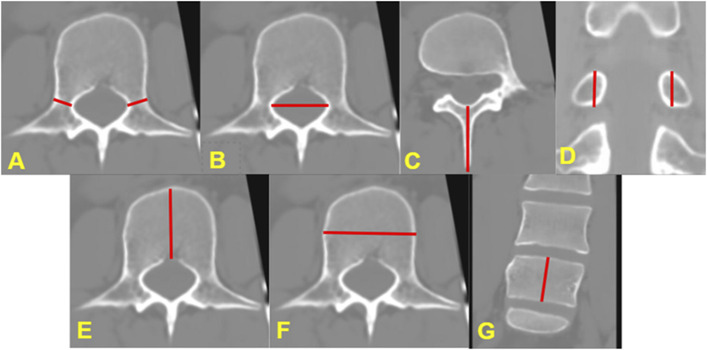

Methods: This was a retrospective chart review of pediatric spine patients at a quaternary care hospital from October 2023 to September 2024. Inclusion criteria included any patients receiving a sCT for spinal evaluation. Patient demographics and imaging results were collected. For any patient with traditional CT (tCT) within 3 months of the sCT (n = 10), osseous anatomical measurements on the coronal, sagittal, and axial sequences were compared (10 total measurements per scan). Official radiology reads were also compared between sCT and tCT.

Results: Twenty-five patients underwent sCT of the spine (2 cervical and 23 lumbar). Indications included rule out congenital cervical anomalies in congenital muscular torticollis (2 patients), spondylolysis (13), spondylolisthesis (2), scoliosis/back pain (4), chronic back pain (4), and back pain with transitional lumbosacral anatomy (4). A total of 176 measurements of spinal osseous anatomy were performed. Comparing tCT with sCT, 62.5% of the measurements differed by less than 0.5 mm, 95.5% by less than 1 mm, and 4.5% differed by 1 mm or more.